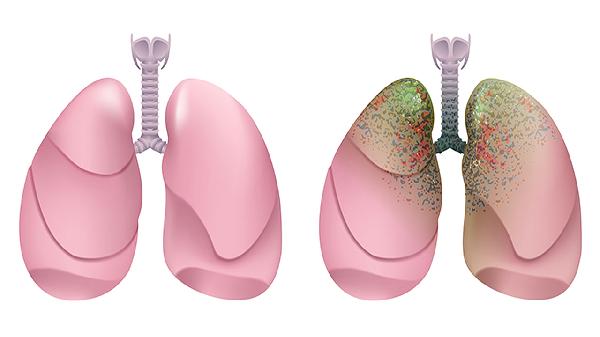

3、肺癌

消癌平片对肺癌有一定治疗作用。肺癌患者常见咳嗽、咯血、胸痛等症状,该药能抑制肺癌细胞扩散,减轻放化疗副作用。临床上多与吉非替尼片、卡铂注射液等药物联合使用,需严格遵循医嘱控制用药剂量。